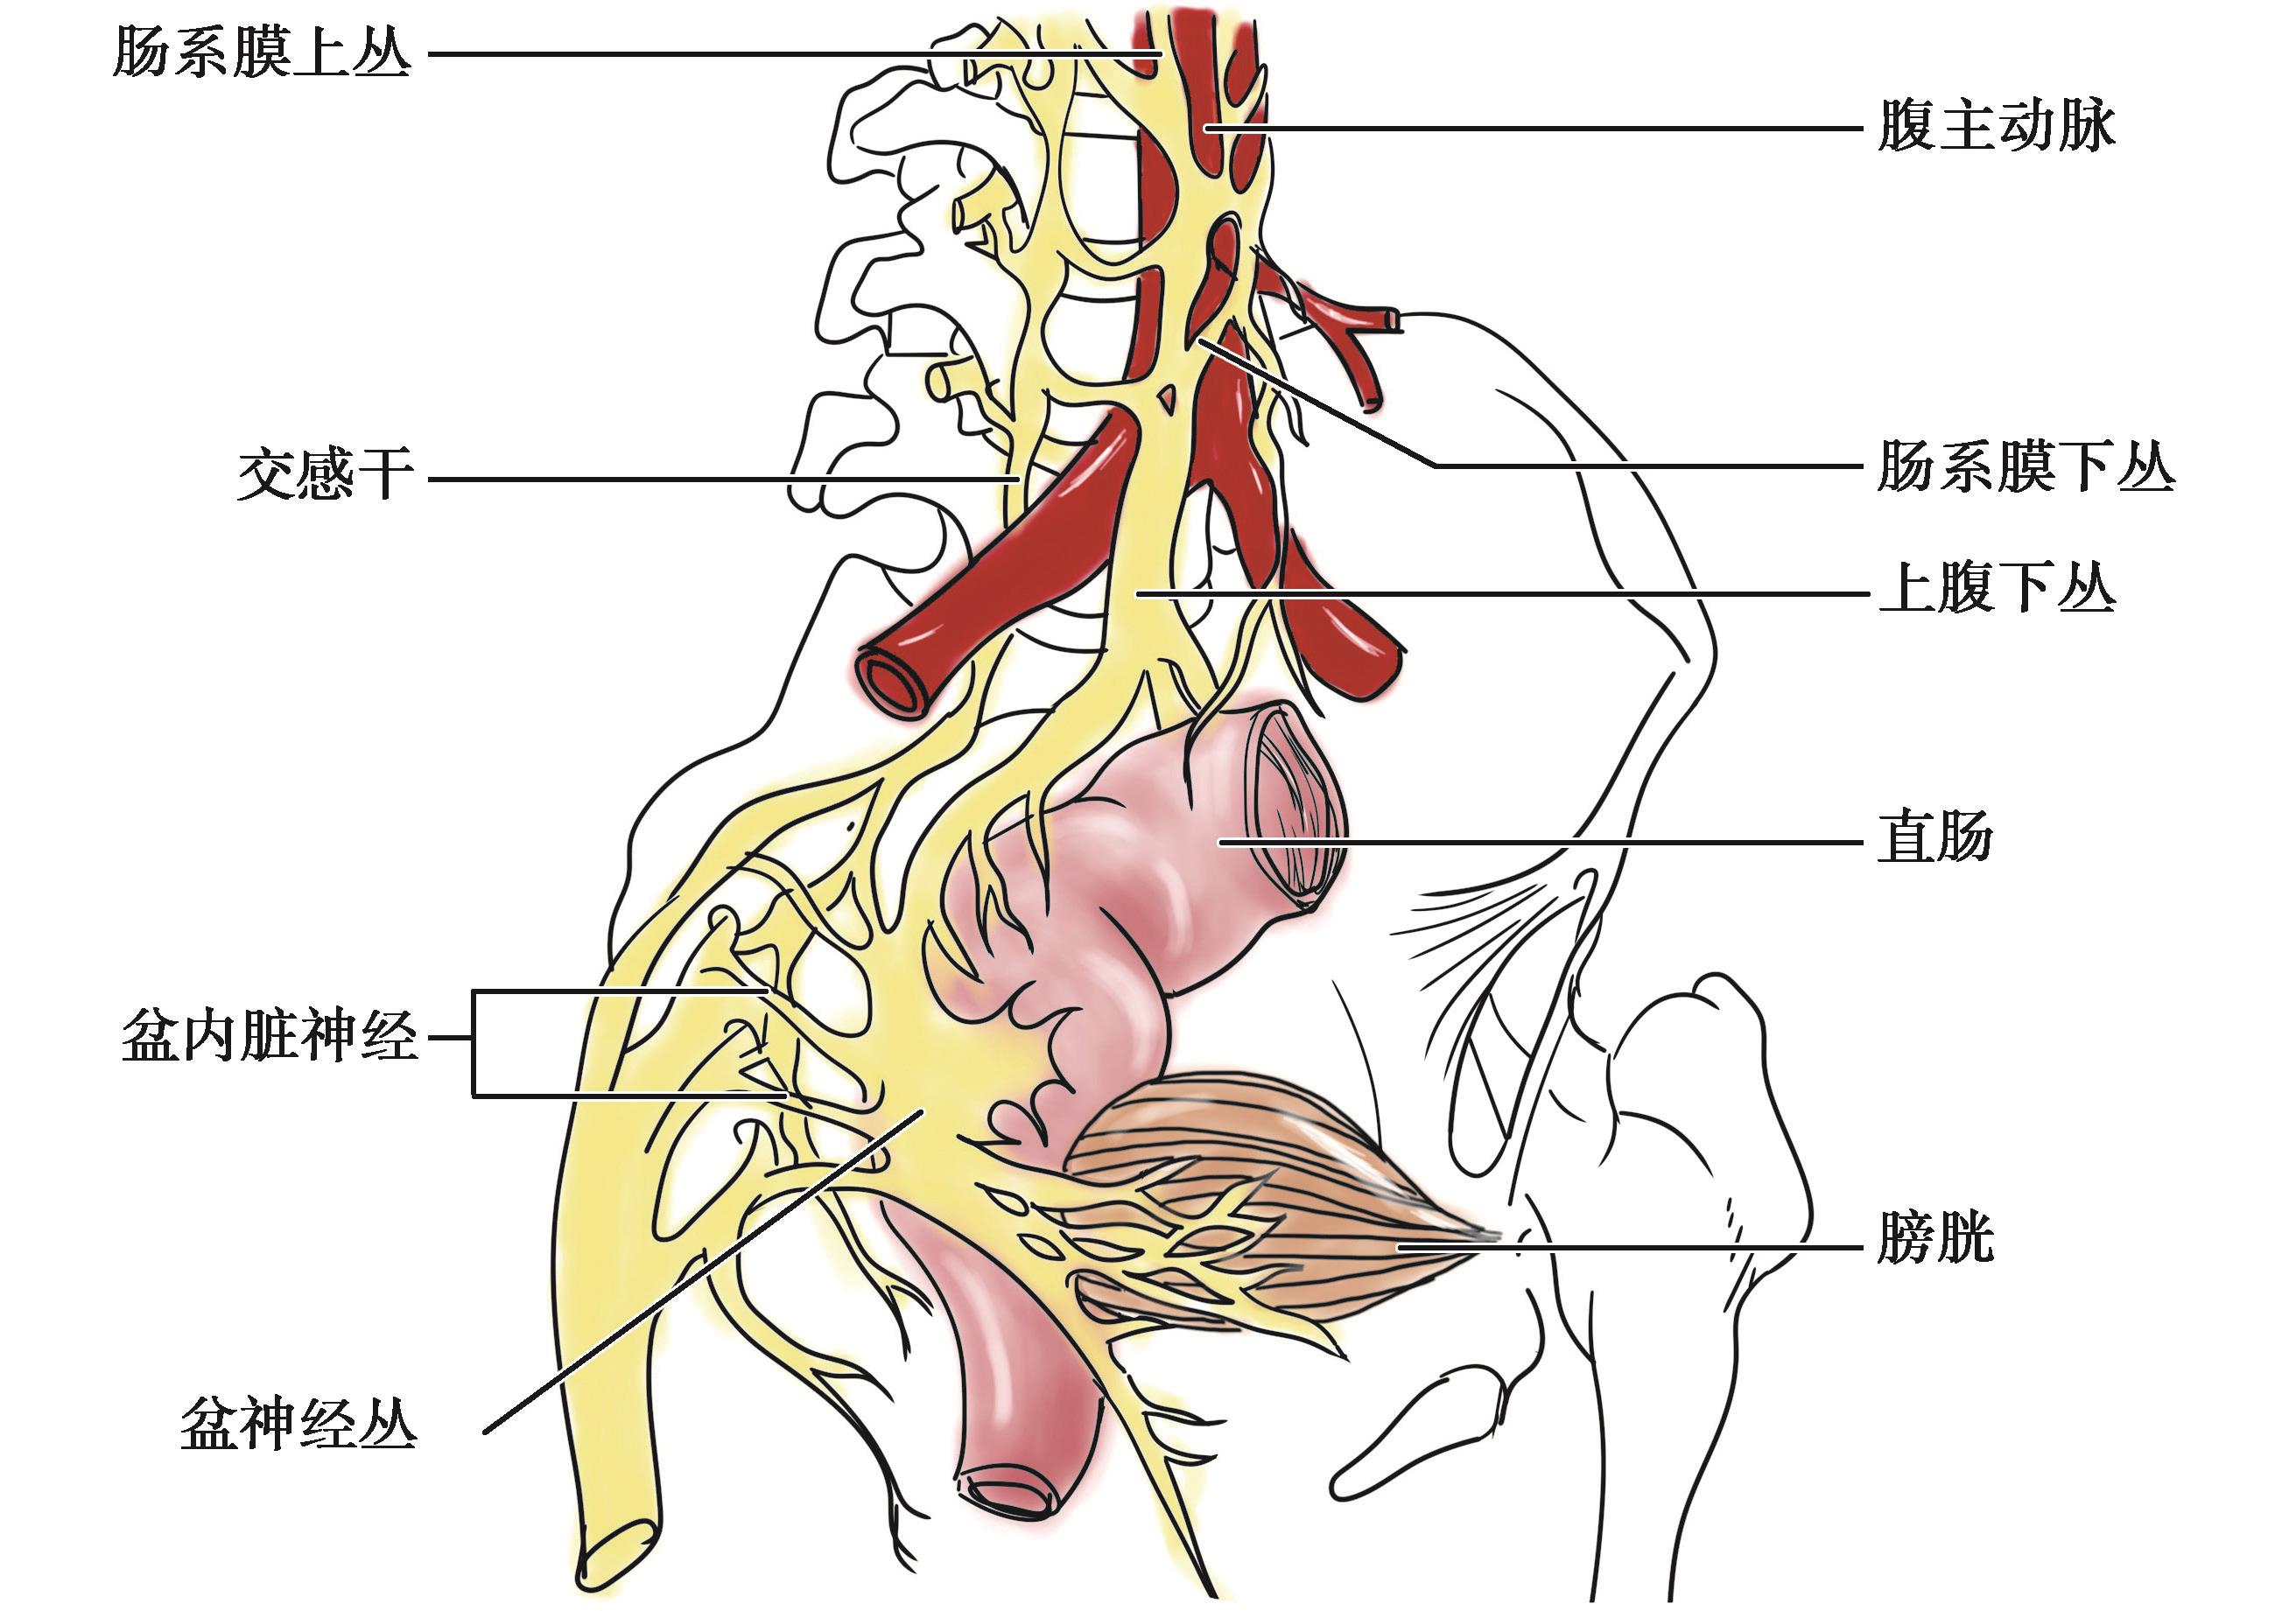

结肠的神经分布见图2-9。

图2-9 结肠的神经

结肠的交感神经主要来源于肠系膜上丛和肠系膜下丛。肠系膜上丛为腹腔丛向下的延续,位于肠系膜上动脉根部。肠系膜上丛的上部有肠系膜上神经节,来自脊髓第10胸节至第3腰节侧角内的交感神经节前纤维在此换元,节后纤维形成次级神经丛,伴随肠系膜上动脉的分支分布于阑尾、升结肠和横结肠右半。肠系膜下丛位于肠系膜下动脉根部,内有肠系膜下神经节。来自脊髓第1~3腰节侧角的交感神经节前纤维在此换元,节后纤维形成次级神经丛,随肠系膜下动脉分支分布于横结肠左半至直肠上部。

右半结肠的副交感神经一般认为来自右迷走神经的腹腔支。该支参加腹腔丛和肠系膜上丛后,伴肠系膜上动脉及其分支分布于盲肠、阑尾、升结肠及横结肠右半。左半结肠的副交感神经来自脊髓第2~4骶节侧角,经骶神经出脊髓后合成盆内脏神经至下腹下丛。这些神经纤维除分布于直肠、膀胱等盆腔器官外,其中部分纤维上行,经上腹下丛到肠系膜下丛,伴肠系膜下动脉及其分支,分布于结肠脾曲、降结肠、乙状结肠及直肠上部。

结肠的传入神经纤维混合在交感和副交感神经(迷走神经或盆内脏神经)中,其神经元胞体在脊神经节或脑神经节内。一般来说,肠的痛觉是经交感神经传导的,该神经纤维的神经元位于脊神经节,并经后根入脊髓。右半结肠痛觉经右侧交感神经传入,左半结肠至直肠乙状结肠交界处的痛觉经左侧交感神经传入,而直肠则经副交感(盆内脏)神经传入。内脏的病变信号传入脊髓低级中枢后可引起相应节段支配范围的牵涉痛,如阑尾炎症的疼痛由内脏感觉纤维经腹腔丛和内脏小神经传入脊髓第10胸节,引起第10胸节躯体感觉分布区域的脐周部位牵涉痛。